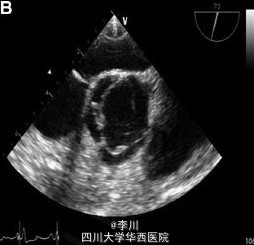

患者,女,35 岁,因车祸入院,既往曾行直肠阴道瘘修补术,诉劳力性呼吸困难多年。面部特征表现为双侧耳前凹陷、脸部不对称。查体提示左侧第二肋间舒张期杂音。血常规、心电图、胸片均未见异常。

结合病史辅助检查、体格检查,诊断为猫眼综合症,予以行主动脉瓣机械瓣置换术治疗。

猫眼综合症是罕见的常染色体异常,核酸排列为 22q11.1q11.21,22 号染色体长臂三体,额外的染色体来源于 22 号染色体近段, 并且带有 2 个染色体的着丝点和双卫星区域。其因有虹膜缺损似猫眼而得名,常表现为眼球异常、缺陷。其他特征包括肛门闭锁、外耳及肾脏心脏多发畸形,临床表现各异。心脏缺陷常表现为肺动脉回流异常和法洛四联症。四叶式主动脉瓣诊断主要依靠超声心动图。该病例中观察到四叶式主动脉瓣及中度升主动脉扩张,冠状动脉无异常。因患者有明显的重度主动脉反流症状,行机械瓣置换术治疗。尽管该患者有罕见的腔静脉连接异常,但其没有血流动力动力学异常,故术中未纠正。患者术后瓣膜功能正常。Circulation 2015.4.10 DOI:10.1161/CIRCULATIONAHA.114.013290.